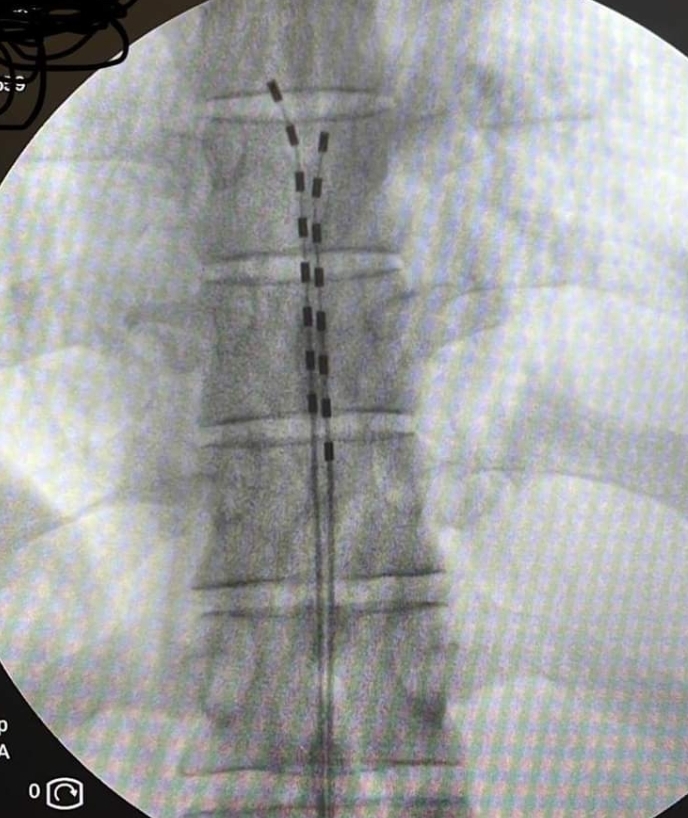

Με τον ασθενή σε πρηνή θέση, υπό τοπική αναισθησία και ακτινοσκοπική καθοδήγηση εμφυτεύονται τα ηλεκτρόδια στον επισκληρίδιο χώρο της σπονδυλικής στήλης και συνδέονται με έναν εξωτερικό διεγέρτη που δίνει τα ερεθίσματα με ένταση που επιλέγεται ανάλογα με τις ανάγκες του ασθενούς. Ο ασθενής για μια περίοδο 7-10 ημερών μπορεί να δοκιμάσει το αποτέλεσμα της διέγερσης και να κρίνει εάν αυτή καλύπτει τις ανάγκες του. Εάν η θεραπεία δεν είναι αποτελεσματική, τα ηλεκτρόδια αφαιρούνται με πολύ εύκολο τρόπο. Επί θετικής απόκρισης, έπεται η διαδικασία τελικής εμφύτευσης του συστήματος.

Με τον ασθενή σε πρηνή θέση και με ελαφρά καταστολή, τα επισκληρίδια ηλεκτρόδια που έχουν ήδη εμφυτευθεί συνδέονται κάτω από συνθήκες πλήρους αποστείρωσης με την γεννήτρια μέσω συνδετικού καλωδίου. Η γεννήτρια εμφυτεύεται υποδορίως στο πρόσθιο ή πλάγιο κοιλιακό τοίχωμα. Κατά τη διάρκεια της διαδικασίας, θα πρέπει να μπορεί ο ασθενής να επιβεβαιώσει τη σωστή κάλυψη των επώδυνων περιοχών.